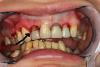

Мирель Опубликовано 8 апреля, 2013 Поделиться Опубликовано 8 апреля, 2013 Здравствуйте. У меня глубокий прикус.(первое фото) Мне ставят коронки на все зубы и при помощи этого немного приподнимают прикус. На переднии верхнии 8 зубов я буду ствить цирконий, на все остальные металлокерамику. 1. Под цирконий решили нервы не удалять, на те которые со штифтами ставить мостом, а на остальные по самостоятельной коронке ( Можно ли так? или следует удалить нервы ...?) 2. металлокерамику ставят в три секции (на нижних зубах, на верхних то что останется тоже под секции)3. сверху с внешней стороны подрезали десну и десневой "сосочек" или "язычек" (незнаю как правильнее). Через день десневой "язычок" с внутренней стороны опух и болит. Врач сказал что он воспален т.к. его травмировали и дня через 3 пройдет. Прошла неделя, опухоль и боль не прошла, гноя нет. Что с ним делать? Почему он опух? (на втором фото стрелочка)4. Нужно ли перелечивать и переделывать все старые пломбы? Ссылка на комментарий